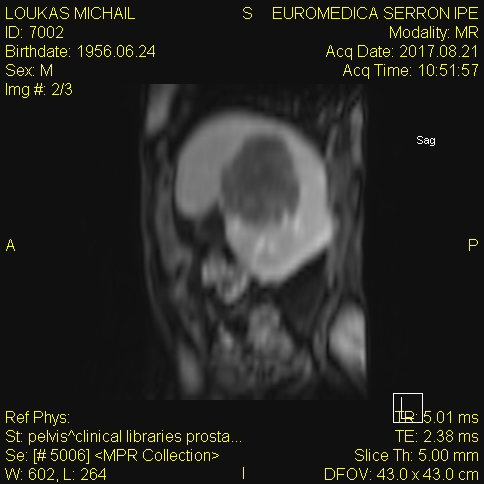

MRCP image confirms the absence of gallbladder and a normal biliary tree (Courtesy Dr. V. Penopoulos)